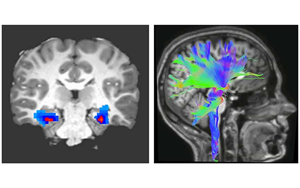

Nature Medicine:一種新的強(qiáng)迫癥神經(jīng)生物標(biāo)志物

貝勒醫(yī)學(xué)院和德克薩斯兒童醫(yī)院最近的一項(xiàng)研究確定了一種特定的神經(jīng)活動(dòng)模式,作為一種新的生物標(biāo)志物,可以準(zhǔn)確預(yù)測(cè)和監(jiān)測(cè)接受深部腦刺激(DBS)治療的強(qiáng)迫癥(OCD)患者的臨床狀態(tài),深部腦刺激是一種迅速出現(xiàn)的治療嚴(yán)重精神疾病的方法。